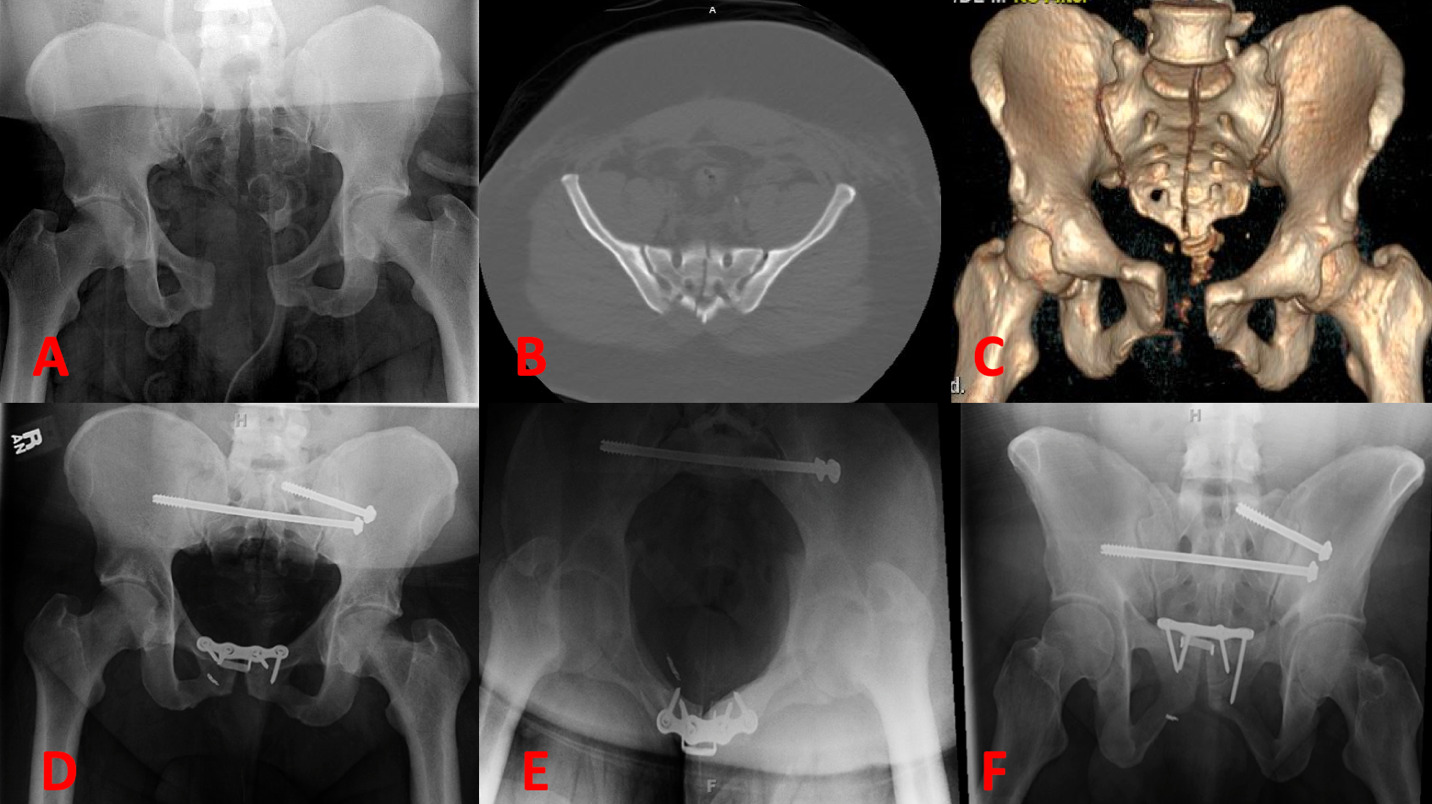

Of note, Zone III fractures can include transverse type fractures or U-shaped fractures, whose fracture lines may cross multiple zones. The Dennis group found 118 (50%) of sacral fractures in Zone I, 81 (34.3%) fractures in Zone II, and 37 (16%) fractures in Zone III. Midline longitudinal sacral (MLS) fractures are very rare fractures isolated to Zone III, and the subject of discussion in this review (Figures 1A-C).

For example, the authors of this paper treated a 41-year-old male (as a 23rd case) with a body mass index of 52. who had sustained an MLS fracture from a motorcycle accident. The patient additionally suffered a sacroiliac joint dislocation, and 3.7 cm pubic symphysis diastasis. The patient was treated with sacroiliac screw, transsacral transiliac screw, and open reduction internal fixation (ORIF) of the pubic symphysis (Fig. 1D-F).

The patient was placed on non-weight bearing precautions for 12 weeks and began ambulating without pelvic pain at 12 weeks post-operatively as is typical for most MLS fracture patients. Of note, the hardware at the pubic symphysis did show signs of early loosening, however his sacral hardware and pelvic ring remained stabled at one-year follow-up.